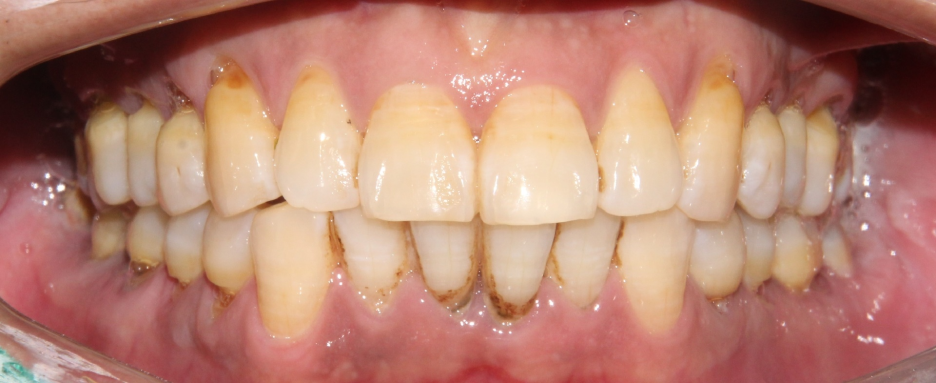

치료해야 될 곳들이 여러군데 보여집니다.

우선 구강 속을 깨끗하게 청소 해 주기 위해

스케일링을 해야 합니다.

그 다음에는 잇몸치료라 하는 치주 소파술(Curettage)를 해야 할 것으로 판단됩니다.

스케일링 만으로는 잇몸 밑으로 자리잡

단단하고 검은 치석과

염증을 제거하기가 어렵습니다.

이런 경우, 국소마취를 하고 큐렛을 이용해서

치석과 염증을 긁어서 빼내는 술식인

소파술을 진행해야 합니다.